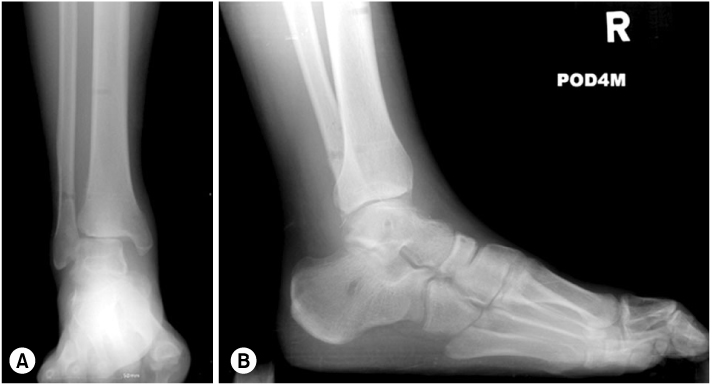

Fig. 8

Follow-up standing ankle radiograph.

Fig. 8 Follow-up standing ankle radiograph.